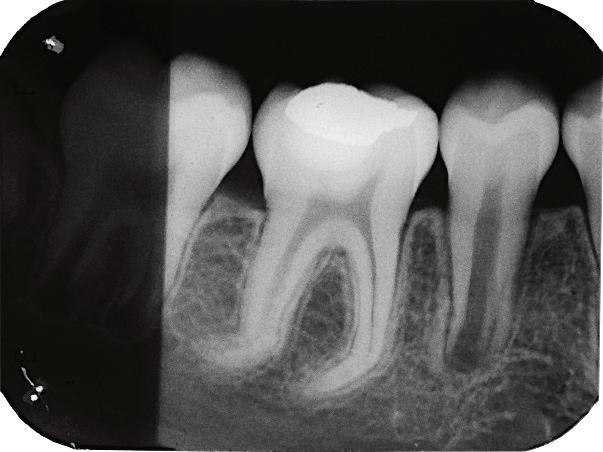

8.Biodentine®AnalternativeinVitalPulpTherapyinYoungPermanentTeeth.ClinicalCase,40monthFollow-Up. (Pgs.88-96)

Biodentine®UnaalternativaenlaTerapiaPulparVitalenDientesPermanentesJóvenes.CasoClínico.Seguimientode40Meses.

LuisDavidRamosFlores,DDS,